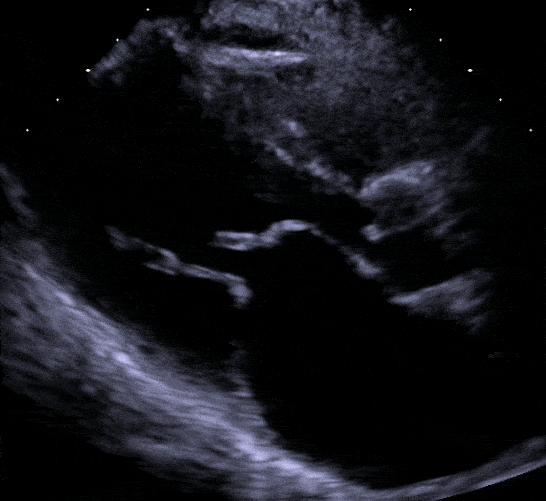

You do a focussed bedside transthoracic ECHO and unexpectedly see on the PLAX (parasternal long axis view) a classical hockey stick / domed appearance of severe mitral stenosis. She also has Pulmonary B-lines (indicating pulmonary oedema) and a flattened interventricular septum, very large atrium & doppler through the tricuspid valve confirms severe pulmonary hypertension.